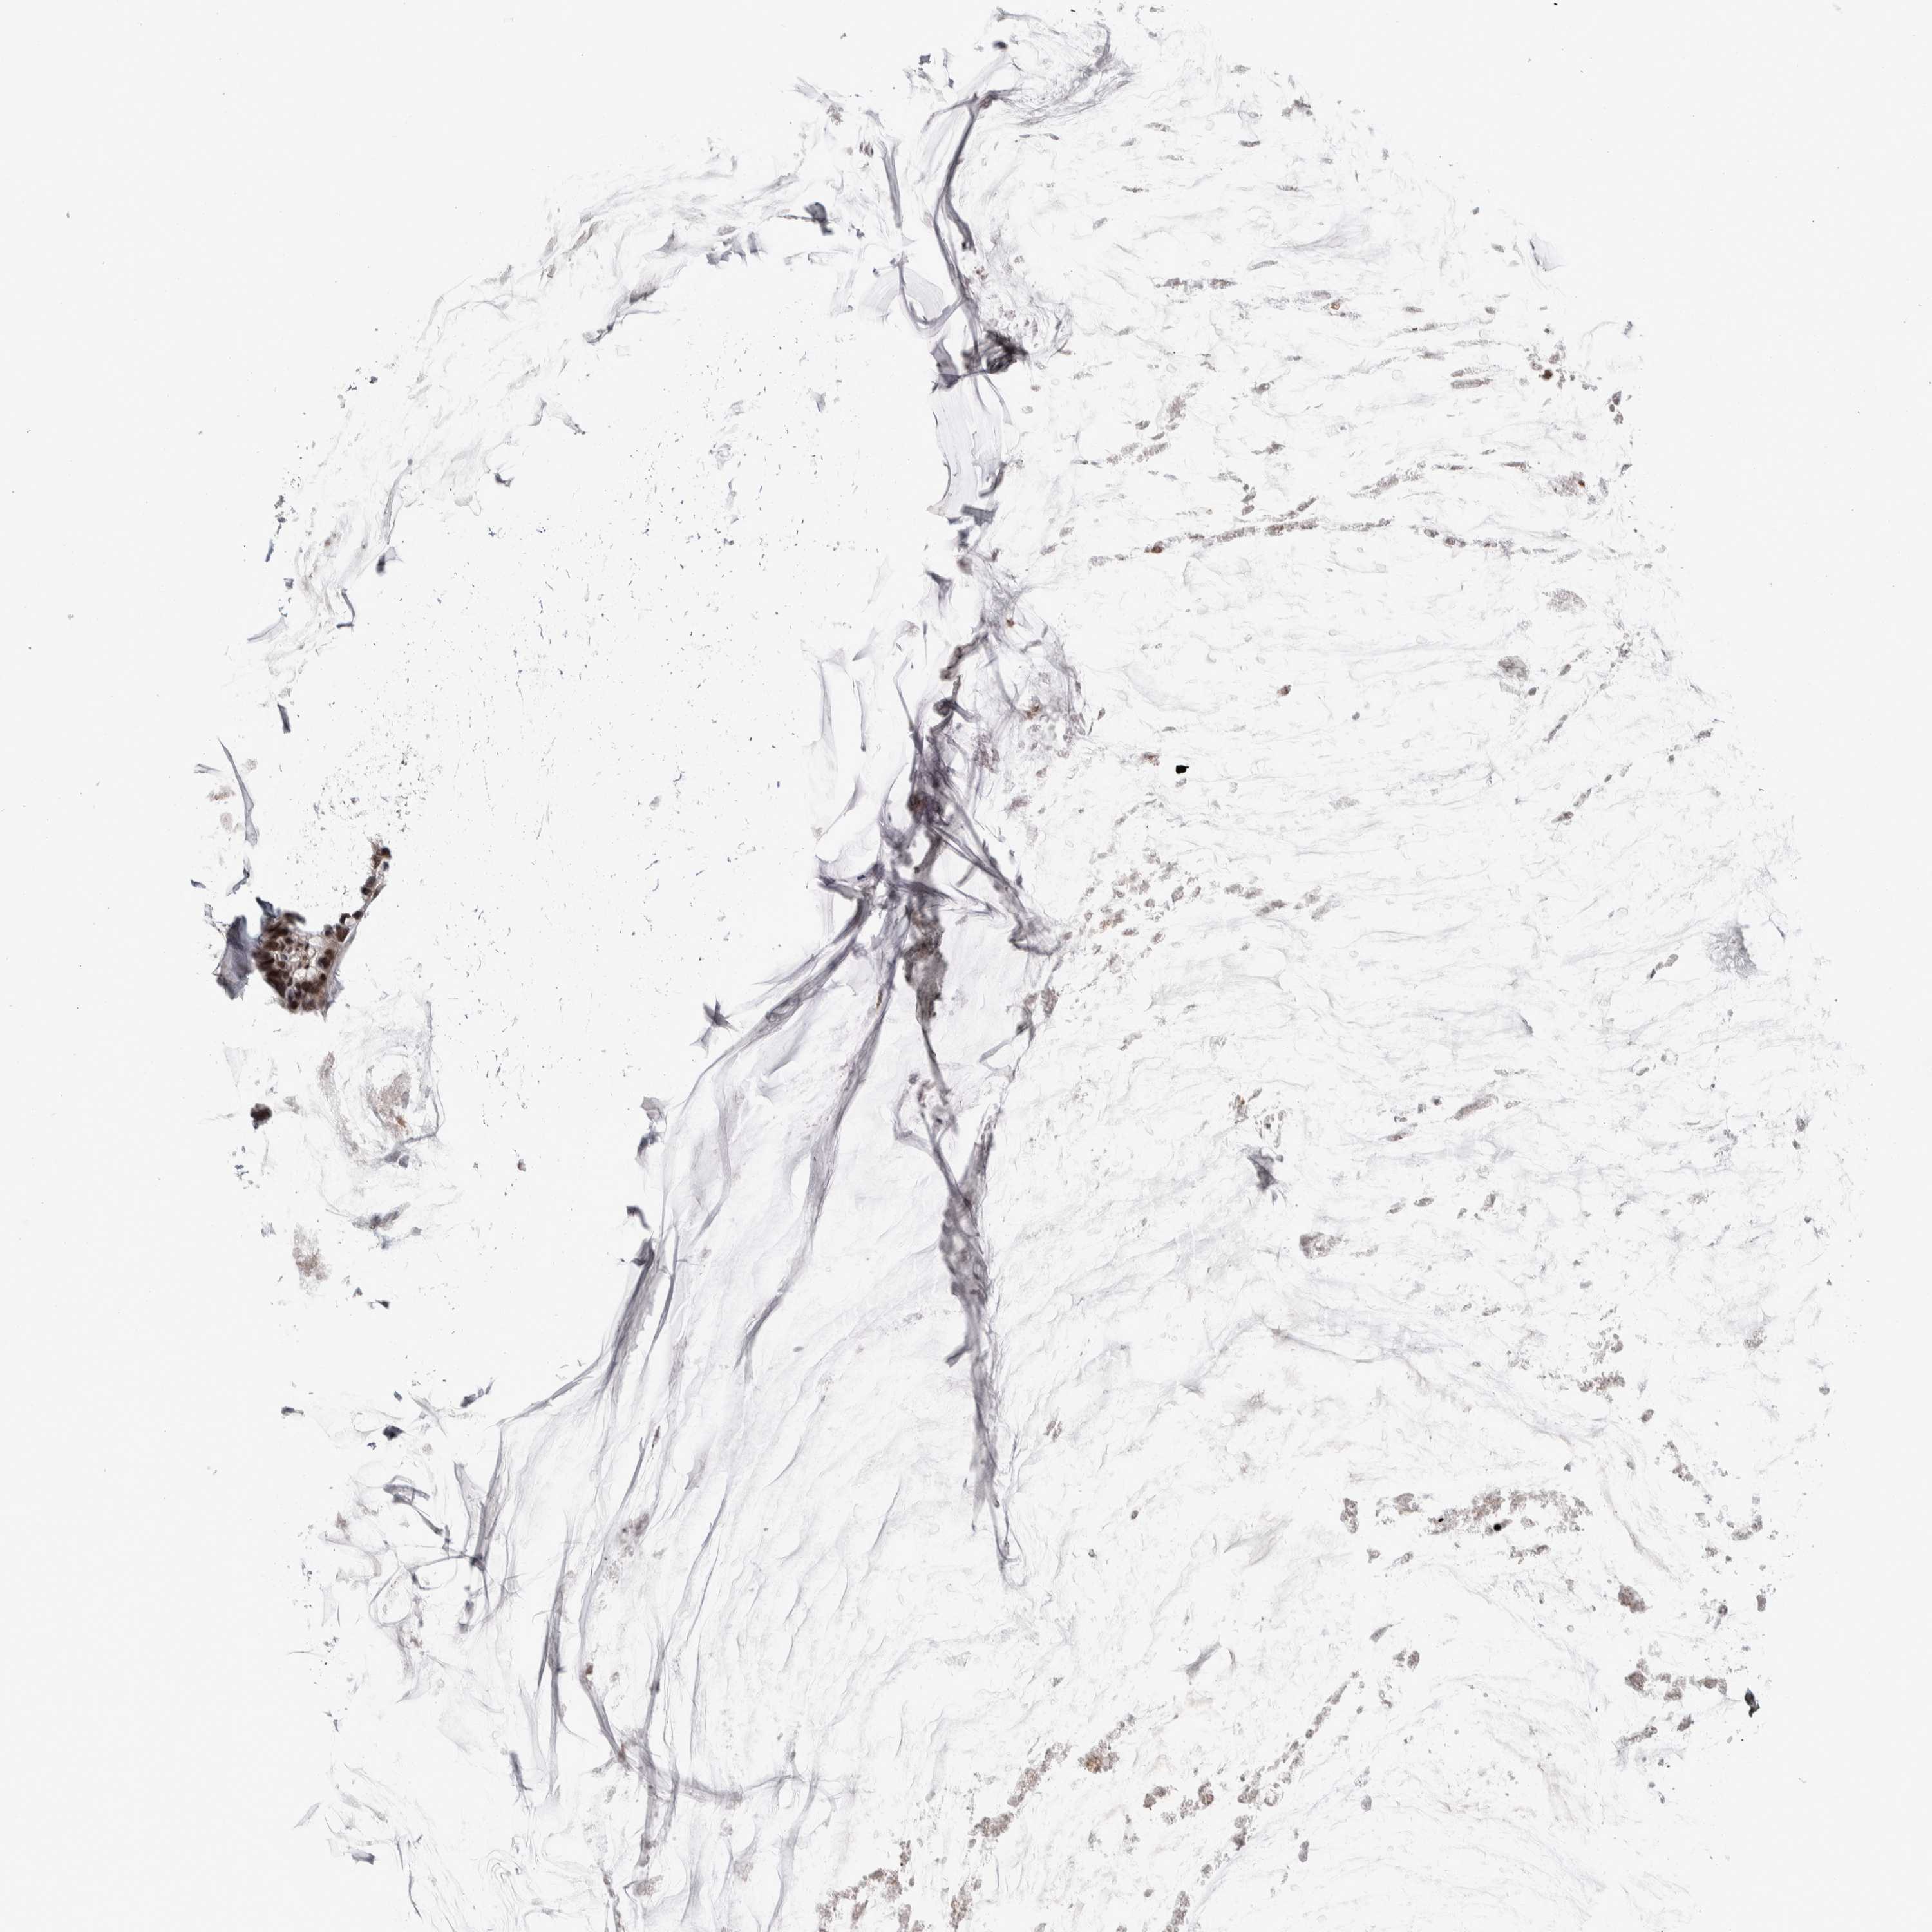

OVARIAN CANCER - Protein expressioni

A mouse-over function shows sample information and annotation data. Click on an image to view it in a full screen mode. Samples can be filtered based on level of antibody staining by selecting one or several of the following categories: high, medium, low and not detected. The assay and annotation is described here.

Note that samples used for immunohistochemistry by the Human Protein Atlas do not correspond to samples in the TCGA dataset.

Antibody stainingi

Antibody staining in the annotated cell types in the current human tissue is reported as not detected, low, medium, or high, based on conventional immunohistochemistry profiling in selected tissues. This score is based on the combination of the staining intensity and fraction of stained cells.

Each image is clickable and will lead to virtual microscopy that enables deeper exploration of all samples and also displays staining intensity scores, fraction scores and subcellular localization as well as patient and tissue information for each sample.

Antibody HPA024230

Carcinoma, NOS